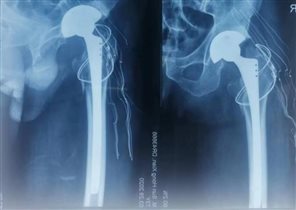

近年来,骨外科开展了我院的多项骨科首例手术,熟练开展髋关节置换手术、老年患者髋部骨折的髓内钉内固定术、胸腰椎体骨质疏松骨折的椎体成型手术、胸腰椎骨折微创内固定术等;在骨科多发伤、复杂骨折、老年患者骨质疏松治疗方面积累了丰富的经验。目前,骨外科成功完成胸腰椎椎体成型术年手术量70余例,可同时做三个椎体成型术,多数患者年龄在70岁以上,80岁以上患者占三分之一,所有患者术后腰背部疼痛均明显缓解。髋关节置换术已成为科室常规手术,髋关节置换年手术量50余例,膝关节置换、关节镜手术近年来手术患者均明显增加。科室能开展所有四肢骨折的手术治疗,年手术量达200余例。

近年来由于老龄患者明显增加,苏纯柱主任针对老年骨质疏松做了大量的工作,对于老龄骨质疏松骨折立足于防治结合,强调对于骨质疏松的早期干预治疗,指导患者规律治疗骨质疏松症。科室治疗的髋关节置换手术患者年龄最大92岁,术后一周患者自己步行出院。腰椎成型术最大年龄患者94岁,患者术后腰痛明显缓解,第二天即可下床活动。老年骨质疏松骨折的快速康复赢得了患者及家属的高度赞扬,提高了患者生活质量,所开展手术取得了患者的广泛认可,赢得了社会赞誉。